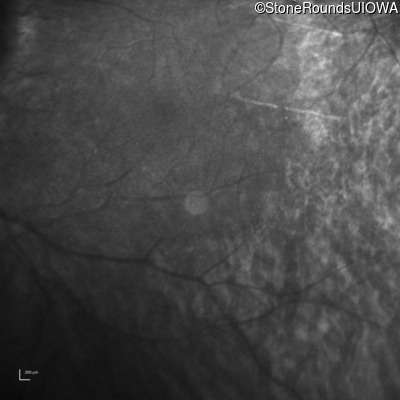

Infrared Fundus Photograph - Right -

No Light Perception

Infrared Fundus Photograph - Left -

Light Perception